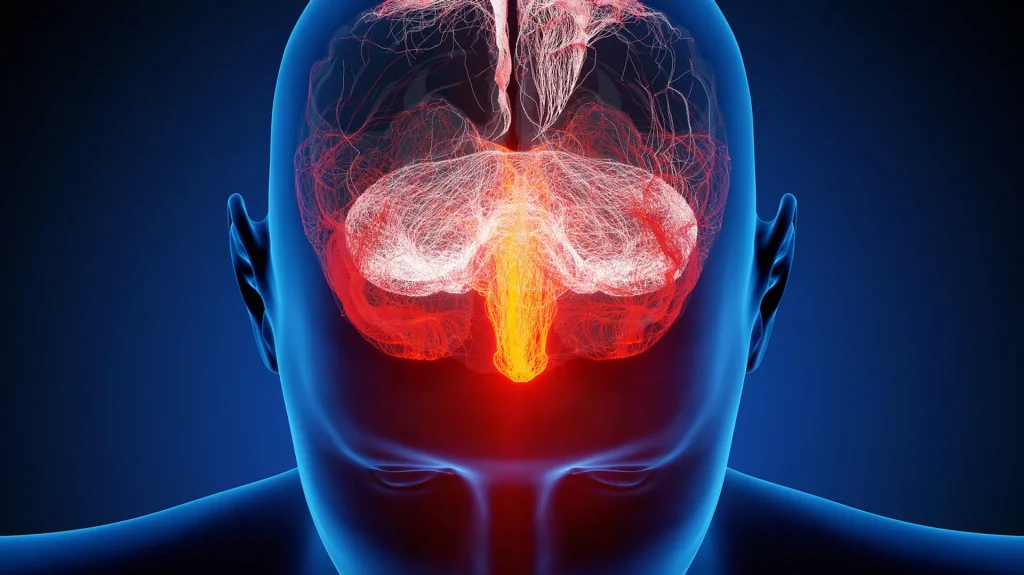

Os cancros cerebrais, e especialmente o GBM agressivo e de rápido crescimento, são particularmente resistentes aos tratamentos contra o cancro. Os cancros cerebrais também matam mais crianças e adultos com menos de 40 anos do que qualquer outra forma de cancro.

Os cientistas acreditam que, como estas células cancerígenas são expostas ao líquido cefalorraquidiano – um líquido que protege o cérebro – elas mudam e tornam-se mais resistentes aos tratamentos convencionais contra o cancro, como a radiação e a temozolomida, um medicamento utilizado para tratar cancros cerebrais.